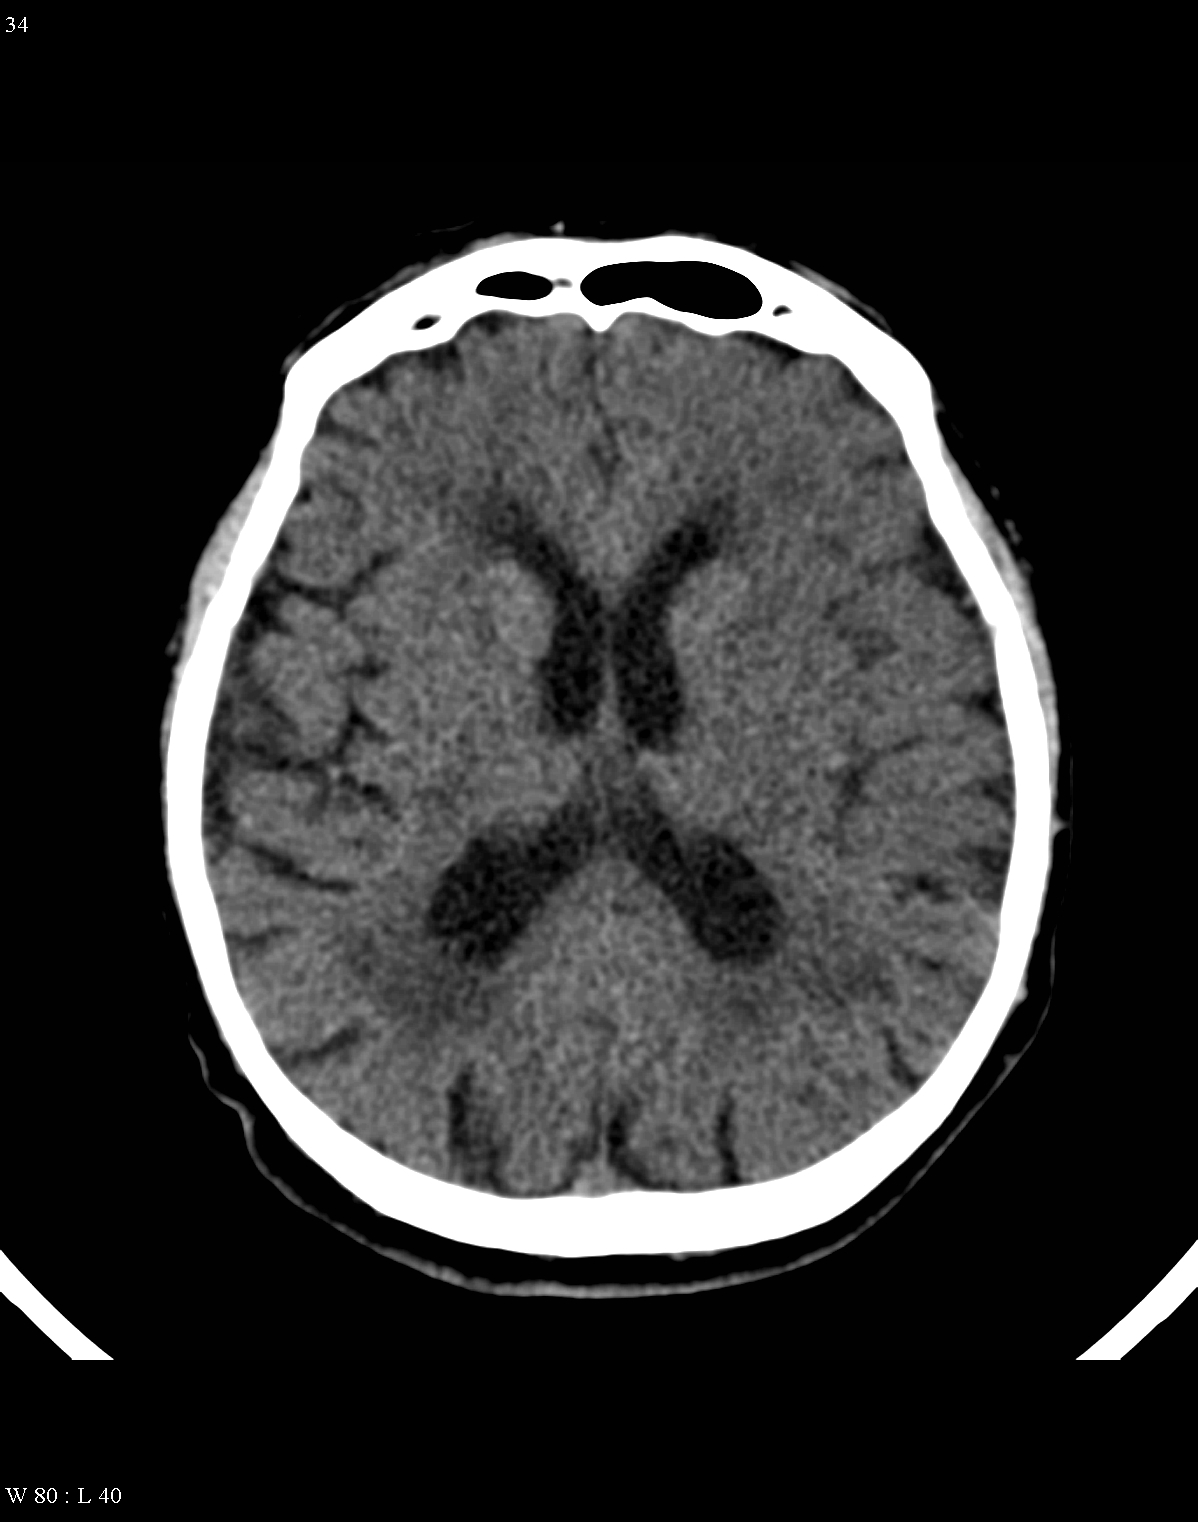

It reliably depicts bony structures, calcifications and cerebrospinal fluid.

It is also capable to distinguish white matter from grey matter, as well as the CSF (0 HU) based on their density differences.

Fresh hemorrhage on CT appears hyperdense, therefore hemorrhagic stroke and subarachnoid bleeding can be promptly diagnosed with CT examinations.

In the chronic phase of the infarct (months to years) the hypodensity of the lesion (CT) reaches the level of the cerebrospinal fluid. There is no more contrast enhancement, the lesion is well differentiated and it degenerates into a cyst secondary to encephalomalacia. The brain parenchyma experiences a volume decrease due to the degeneration (sometimes calcifications can occur at the marginal border of the infarct).